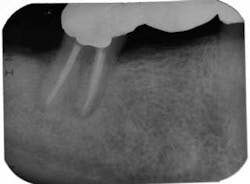

On the second appointment, the calcium hydroxide was rinsed out and the canals reinstrumented. QMix was again placed into the canals and agitated with EndoActivator. The canals were filled using warm vertical condensation with System B and Calamus backfill. The patient was given a six-month follow-up appointment and ibuprofen 600 mg for postoperative discomfort. I again stressed to the patient that the prognosis for this tooth was guarded. At the six-month follow-up appointment, the patient had been asymptomatic and there was clear evidence of healing.